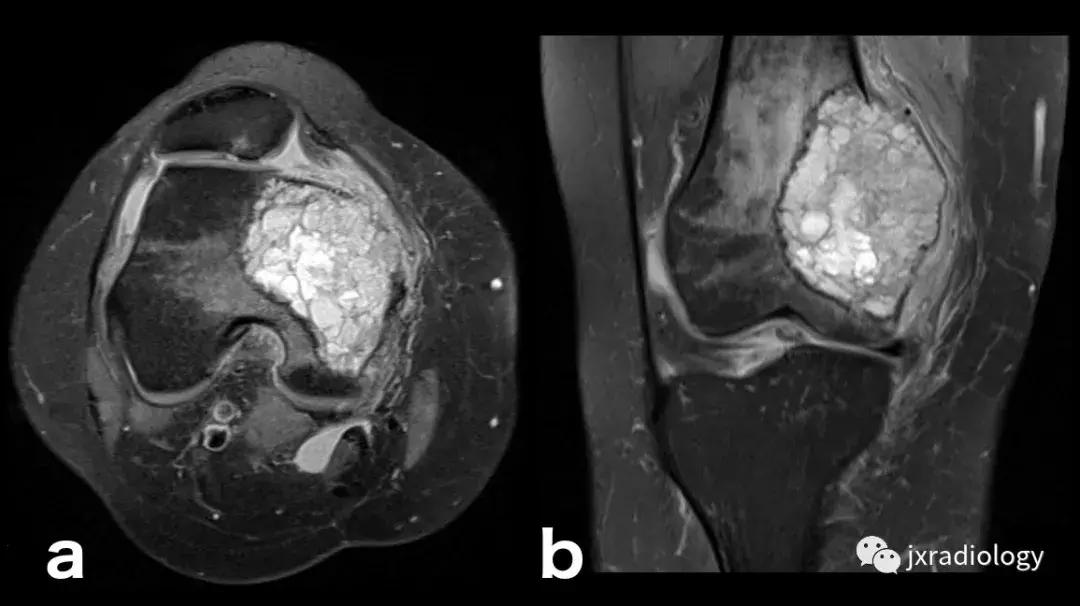

图24:骨样骨瘤:在这些良性肿瘤中,水肿可以继发于前列腺素E2引起的炎症反应(a,b:横断位和冠状CT扫描; c,d:横断位T1-WI和冠状位PD-FS-WI)。